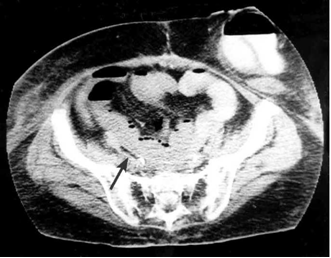

בטומוגרפיה ממוחשבת של הבטן ניתן לראות גז בדופן המעי הנגוע ונוזל בין לולאות המעי. אוויר במערכת השערית נראה באיכות הטובה ביותר בטומוגרפיה ממוחשבת (תצלום 22.4).